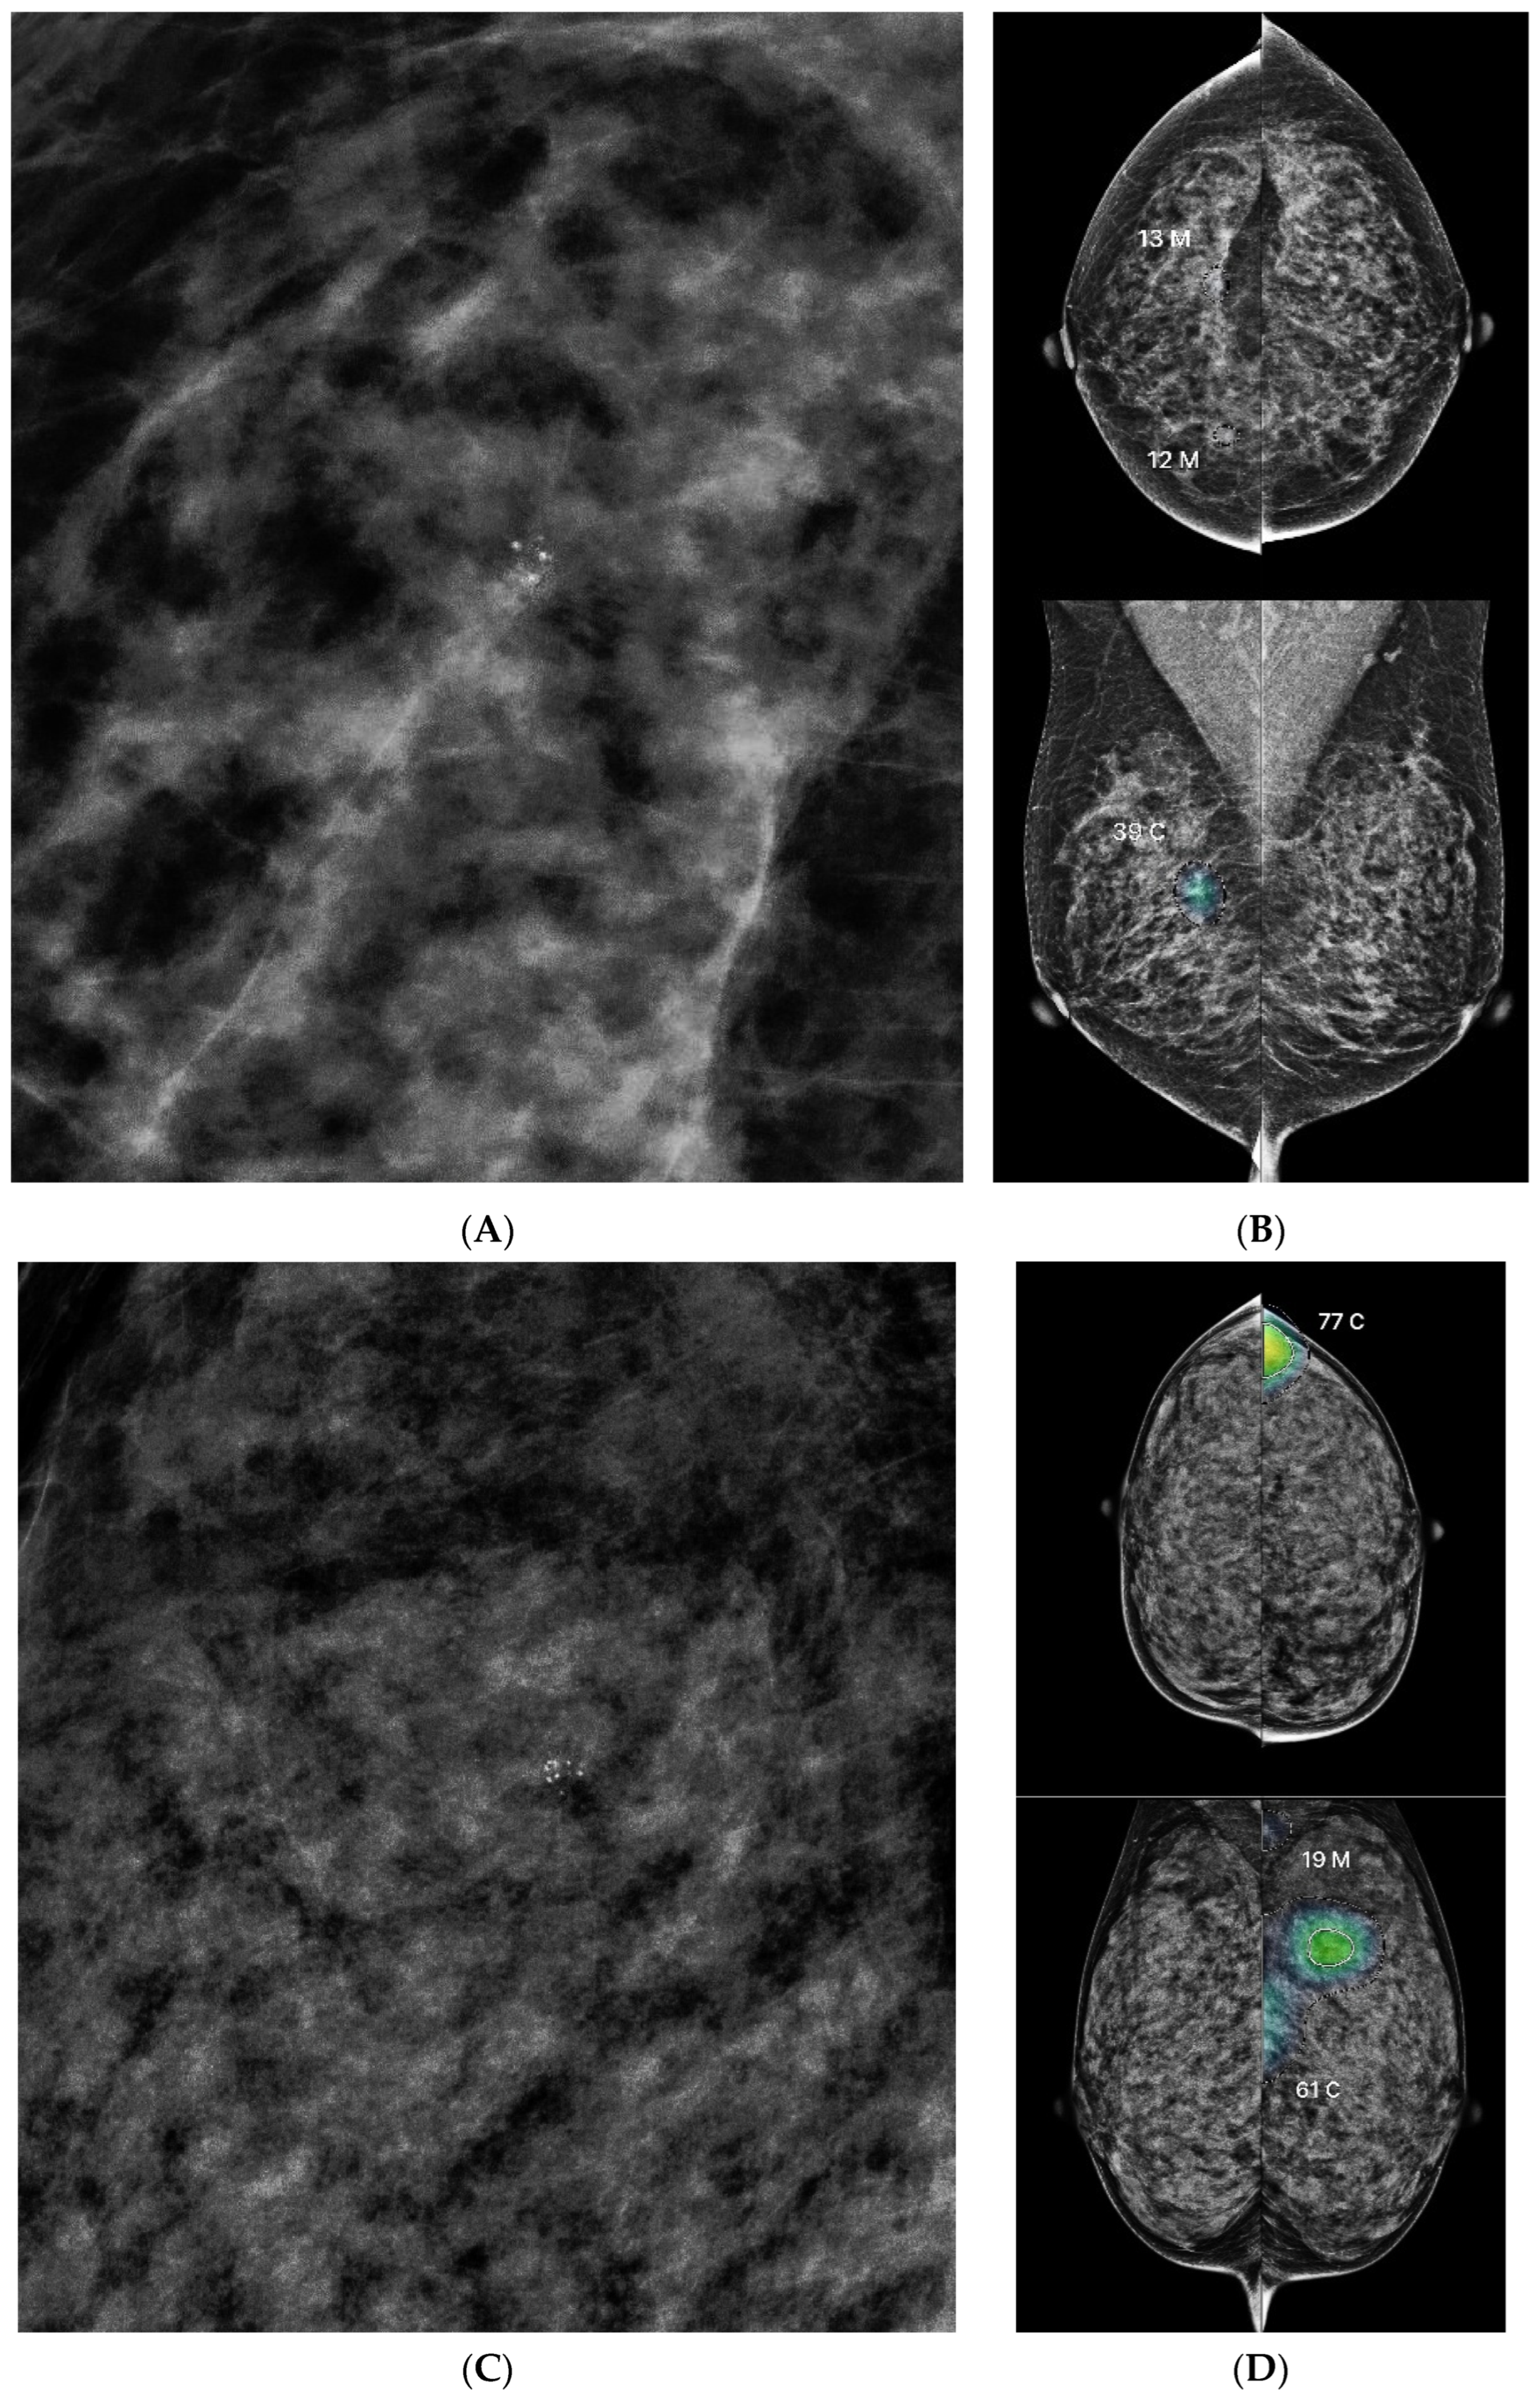

3.3. Lesion Characteristics and AI Score Correlation

3.4. ROC Analysis and Threshold Optimization

3.5. Discordance Analysis Between AI and Radiologists

4. Discussion